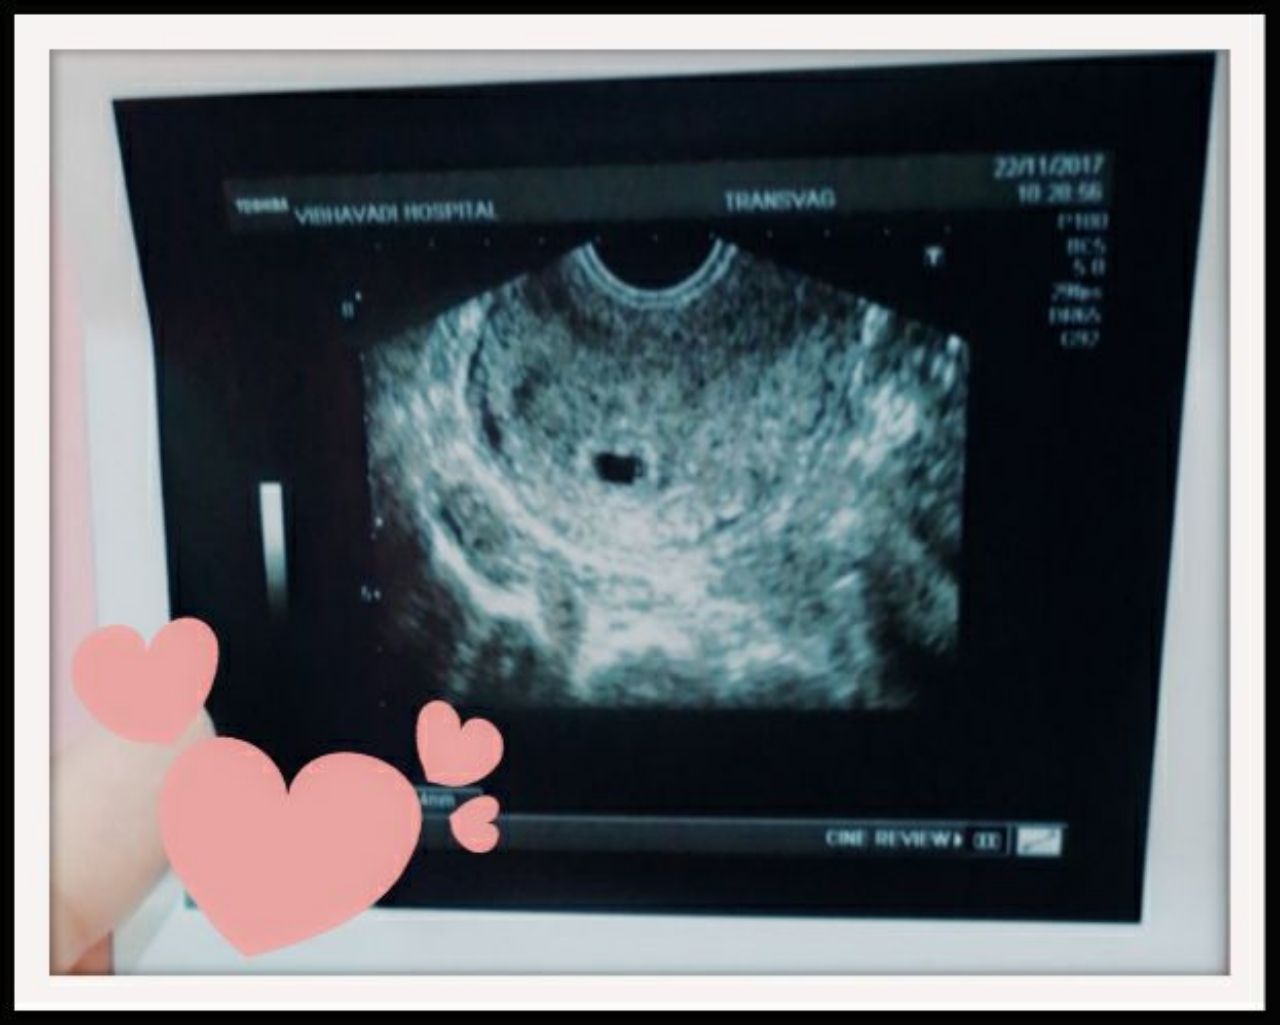

โดย ชมพู่ ได้โพสต์ภาพอัลตราซาวนด์และเขียนข้อความในเฟซบุ๊กส่วนตัวว่า "ตอนแรกยังไม่กล้าพูดเต็มปากเท่าไร กลัวจะยังไม่ชัวร์เพราะยังอัลตราซาวนด์ไม่เห็นถุงการตั้งครรภ์ เนื่องจากอายุครรภ์ยังน้อยมาก กังวลมาก นอนหลับไม่สนิทเลยสักคืน จนวันนี้ได้เห็นถุงการตั้งครรภ์ ได้เห็นไข่แดง ซึ่งแปลว่ามีการฝังตัวของตัวอ่อนอย่างแน่นอน แน่ใจแล้วว่าไม่ท้องนอกมดลูก 100% น้ำตาไหลถึงจะมีลูกมาแล้ว 2 คน แต่ความรู้สึกก็ยังปริ่มๆ ล้นๆ ข้างในหัวใจ ดีใจที่รู้ว่าลูกปลอดภัย ณ วันนี้ก็ 5w พอดิบพอดี ฝากเนื้อฝากตัวน้องนุชคนสุดท้องด้วยนะค้า ใครมีของกิน ของดอง ของเปรี้ยว อาหาร ขนมอะไรก็ได้ แม่ยินดีรับมากนะคะ 555 แม่หิวมาก แม่ต้องการการบำรุง #ฝากร้านได้นะค้าวันนี้แม่อารมณ์ดี"

ภาพอัลตร้าซาวนด์ลูกคนที่ 3 ของเอ๊ะและชมพู่

ถามถึงเรื่องที่ชมพู่โพสต์ภาพอัลตราซาวนด์และบอกว่าท้องได้ 5 สัปดาห์แล้ว?